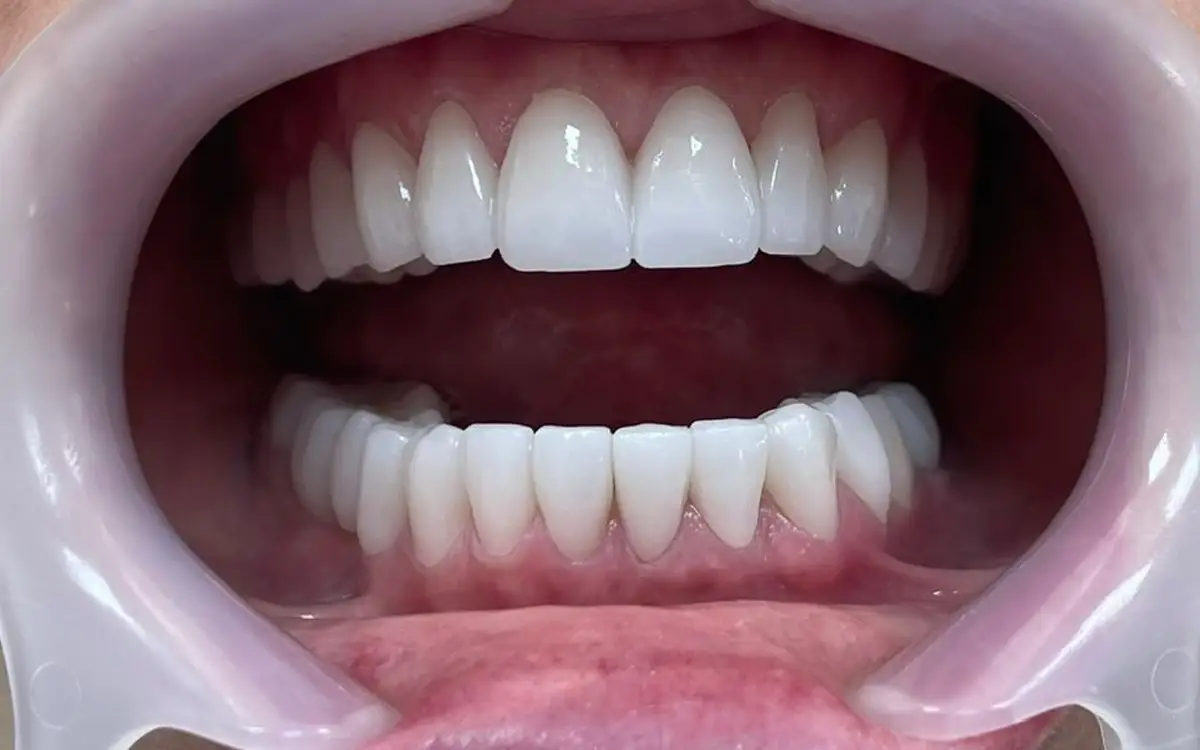

Smile After Smile Before

Smile After Before

After dental treatment 1

After dental treatment 2

After dental treatment 3